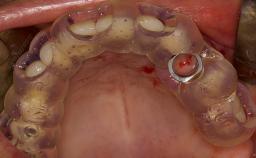

• describe the surgical treatment concept and steps for the lateral SFE technique and assess the prognosis of this procedure

• discuss the grafting materials used in lateral SFE and the indications for use of membranes